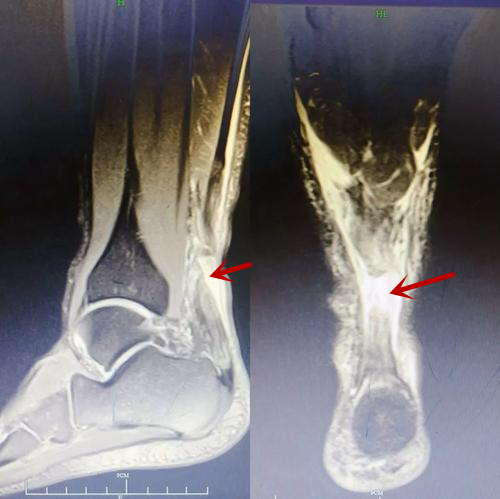

当然,除了满足跟腱断裂的特点以及体检以外,闭合性跟腱断裂诊断的金标准还是核磁共振。因为核磁共振对软组织很敏感,可以直接看到断裂的跟腱,如下图:

跟腱断裂核磁共振